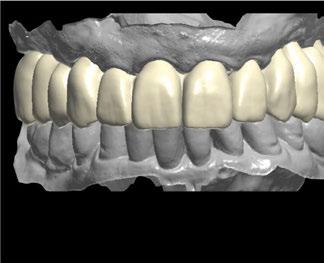

1. Planificación digital y diseño de la férula de cirugía guiada Tras analizar el caso y siguiendo los parámetros estéticos y funcionales, se realizó un encerado digital de la arcada superior mediante el programa de diseño 3D Exocad® (Figura 5), el cual se imprimió y validó junto al paciente mediante un mock-up (Figura 6 a-b).

A continuación, para la planificación de los implantes dentales y el diseño de la férula de cirugía guiada se usó la plataforma digital RealGUIDE®. Para ello se realizó el matching, por un lado, del archivo STL del encerado digital; y, por otro, del archivo 3D. De esta manera, se pudo analizar el tejido óseo residual apical a cada diente y la posición de la raíz respecto a las corticales vestibular y palatina. También se estudió la relación de los contornos óseos con los tejidos blandos y con la posición final de los márgenes cervicales de la restauración protésica, pudiendo así planificar la posición 3D correcta de los implantes. En esta primera fase se diseñó una férula quirúrgica para la elevación de seno bilateral a partir del software RealGUIDE™, que nos sirvió de guía para el diseño de las ventanas de acceso. Esta férula se imprimió con la impresora 3D Formlabs® (Figura 7)

Figura 5. Encerado digital del caso.